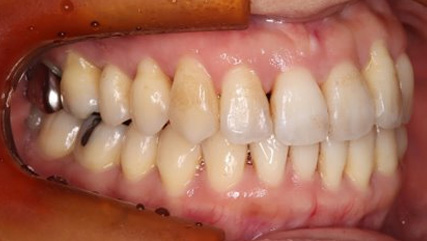

下顎が上顎より前に出ている状態です。お顔つきも、下顎の先(オトガイ)が前に出ているような横顔になる場合が多いです。前歯が咬んでいないことが多く、奥歯への負担が大きい状態になります。そのままのかみ合わせを続けてしまうと、奥歯がかけたり、割れたりするリスクが高まります。歯列矯正では奥歯の位置をコントロールし、前歯のかみ合わせを作る治療方針を立てます。ごく稀に、歯列矯正ではかみ合わせを作れない場合もあり、その場合は外科矯正という手段を用いて矯正治療をしなければいけません。受け口は、遺伝性が強いとも言われておりますので、そういった情報も考慮し、治療を進めていくことが大切です。

治療前

治療終了前